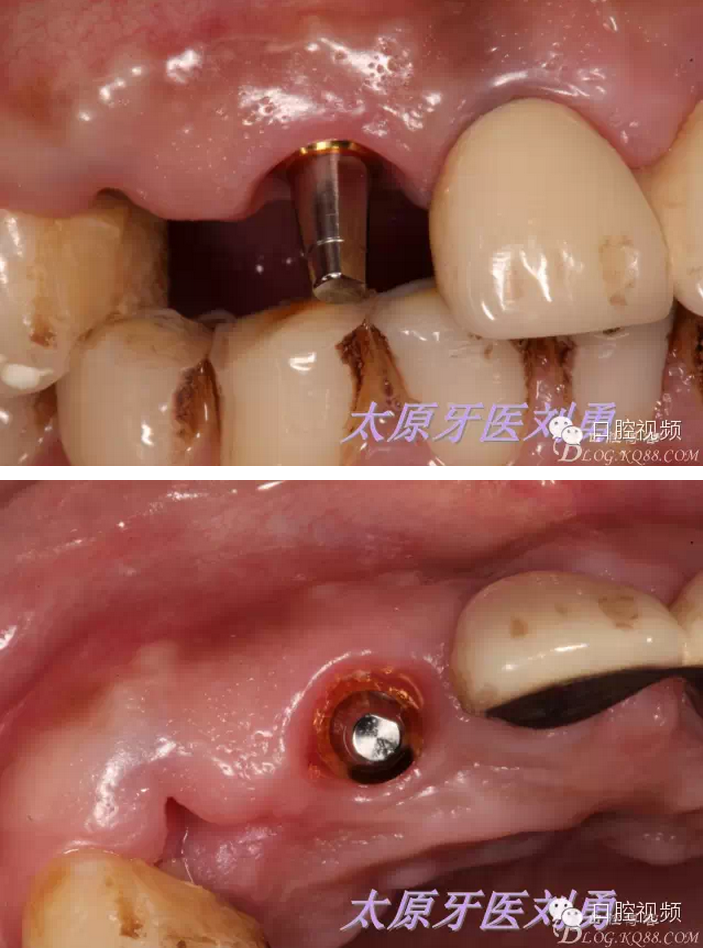

口內(nèi)檢查可見A23殘根,根面齲壞至齦下較深,局麻下,高速手機(jī)+加長金剛砂車針+球鉆,去除A23腭側(cè)牙根,保留唇側(cè)根壁,并修整,徹底刮治牙槽窩,沖洗后,偏腭側(cè)方向預(yù)備并植入種植體,種植體與唇側(cè)根壁之間隙植入biooss骨粉,初期穩(wěn)定性良好,上實心基臺,制作臨時冠引導(dǎo)牙齦成形。術(shù)后患者無水腫,且疼痛較輕。如下圖:

術(shù)后20天,患者A3松動,給予取出種植體,同時探查A3種植窩,可探及周圍骨壁完整,重新制作臨時冠,口內(nèi)檢查A2周圍牙齦健康,給予x片檢查,可見A2種植體周圍正常,A3唇側(cè)根壁可見顯影,并可看到根充物顯影,故考慮A3失敗原因應(yīng)該在于根充物污染導(dǎo)致骨壁感染,因此在以后類似技術(shù)中在拔除腭側(cè)根壁后一定要進(jìn)行X片檢查,排除可能導(dǎo)致失敗的原因。如下圖:

術(shù)后45天,患者再次復(fù)查,可見A2牙齦成形非常良好,保持了天然牙齒的穿齦形態(tài),種植體穩(wěn)定性也良好,如下圖